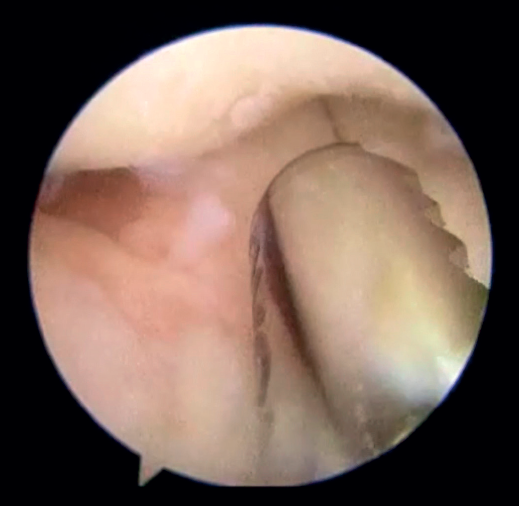

Técnica quirúrgica de la artrólisis artroscópica en un codo postraumático

La técnica es similar a la descrita por O’Driscoll o Pederzini(19,22) bajo anestesia plexual. Con el paciente colocado en decúbito lateral y con manguito de isquemia en la raíz del miembro, este se coloca en un soporte que permite que el hombro esté a 90° de abducción y el codo a 90° de flexión. Se marcan las referencias (Figura 1) (ambos epicóndilos, olécranon, tendón del tríceps, septo intermuscular medial, cúpula radial y soft spot) y, si se dan las condiciones explicadas previamente, se libera el nervio cubital a través de un abordaje posteromedial de escasos 3 cm que permite liberar por completo y movilizar al nervio para realizar el portal proximal medial con seguridad (Figura 2) y, en caso de déficit de flexión, seccionar la banda posterior del ligamento colateral medial. Una vez liberado el nervio, se insuflan entre 20 y 40 cc de suero salino fisiológico a través del soft spot (centro del triángulo formado por el epicóndilo lateral, la cúpula radial y el olécranon) para distender la articulación y disminuir el riesgo de lesión neurovascular(23). En caso de tener que trabajar en el compartimento posterior por adherencias tricipitales o capsulares que impidan la flexión o por ocupación de la fosa olecraneana por fibrosis o cuerpos libres que impidan la extensión (Figura 3), hay autores que defienden iniciar la artroscopia por la cámara posterior para evitar el edema que aparece en las partes blandas posteriores durante el trabajo en la cámara anterior que dificulta el trabajo final en la cámara posterior(19,22). En este caso, realizaremos 2 portales posterolaterales o un portal directo en el soft spot y otro posterolateral que nos permitan buena visión, seguir la gotiera lateral en sentido proximal y realizar exéresis del tejido que esté ocupando la fosa olecraneana, resecar la punta del olécranon si fuera necesario y el tejido cicatricial de la gotiera lateral y de la articulación radiocubital proximal posterior (Figura 4) y despegar el tríceps del húmero si existieran adherencias. En el compartimento posterior en algunos casos (codos de pequeño tamaño, gran ocupación de espacio) puede ser útil emplear la óptica de pequeñas articulaciones, aunque en la gran mayoría de los pacientes se puede usar el artroscopio de 4,5 mm y 30°.